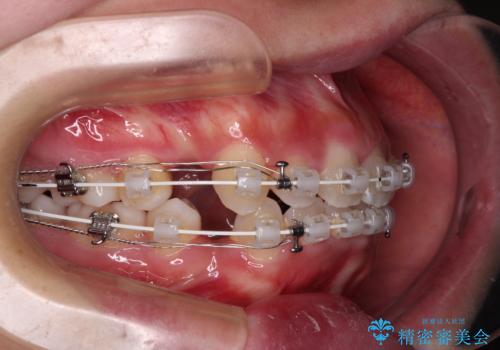

- 矯正装置

- 審美装置

- 治療期間

- 5年3ヶ月

- 治療回数

- 30回以上